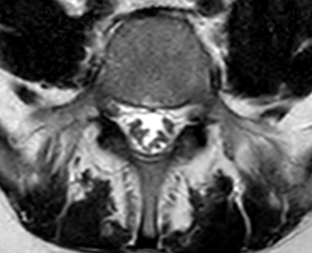

Se toman imágenes de control observando progresión de processo inflamatório a nível cerebral y a nível lumbar (figuras 4 y 5), progresión de siringomielia com afectación a nível cervical (figura 6)

Mayor agrupamento de raíces a nível lumbar.

Figura 5